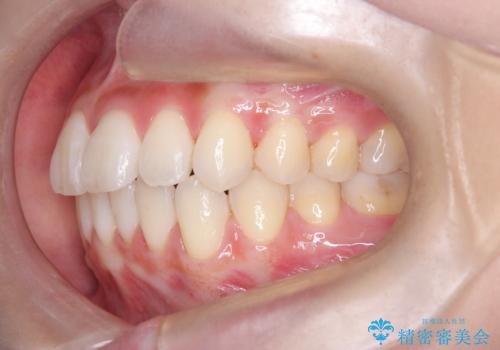

反対咬合を治したい。インビザライン

インビザラインにて臼歯の遠心移動を行いながら、スペースを作り反対咬合を改善することができました。

反対咬合はインビザラインの方が治しやすい場合もあります。